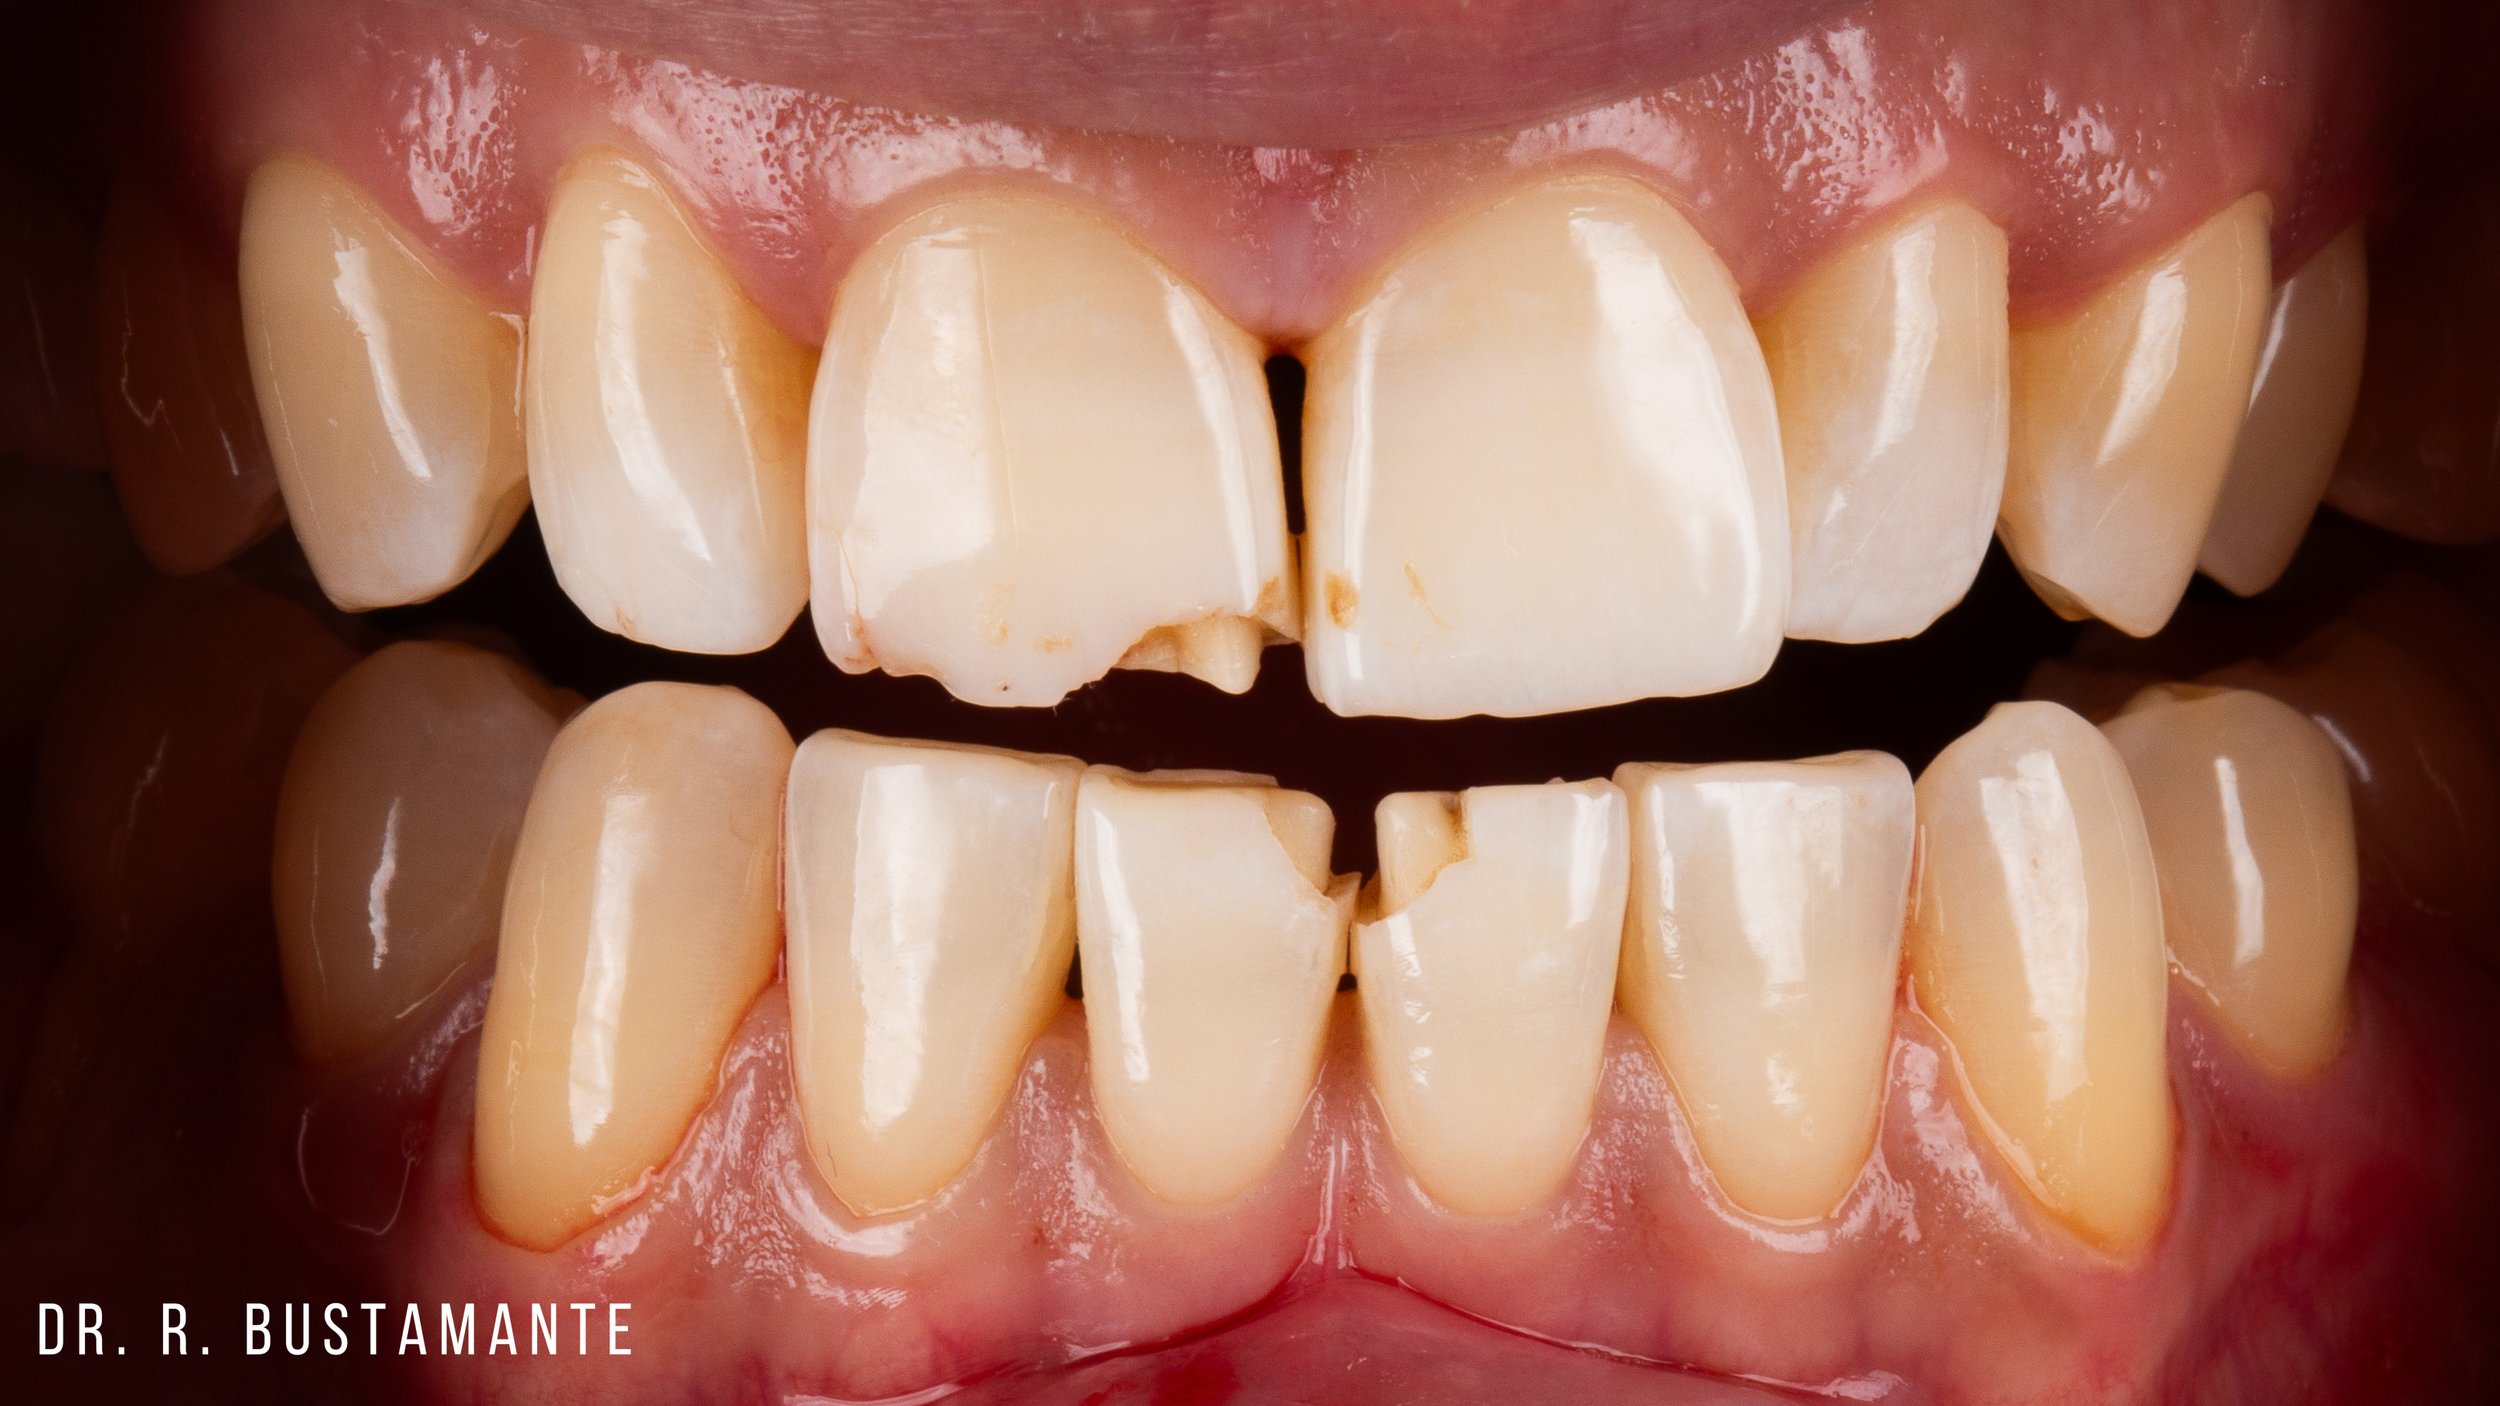

Bioclear offers a transformative solution for enhancing your smile. Whether you’re looking to close small gaps between your teeth (commonly known as black triangles), address uneven, chipped, or broken teeth, or refresh worn, discolored, or decayed teeth, Bioclear delivers natural, stunning results tailored just for you.

The Bioclear Method can rejuvenate the shape, size, and fit of your teeth. Bioclear is a minimally invasive, conservative alternative to rejuvenating worn out, broken, discoloured, and chipped teeth.

Repairing damaged or worn teeth.

Repairing a chipped or discolored tooth with Bioclear Veneers.